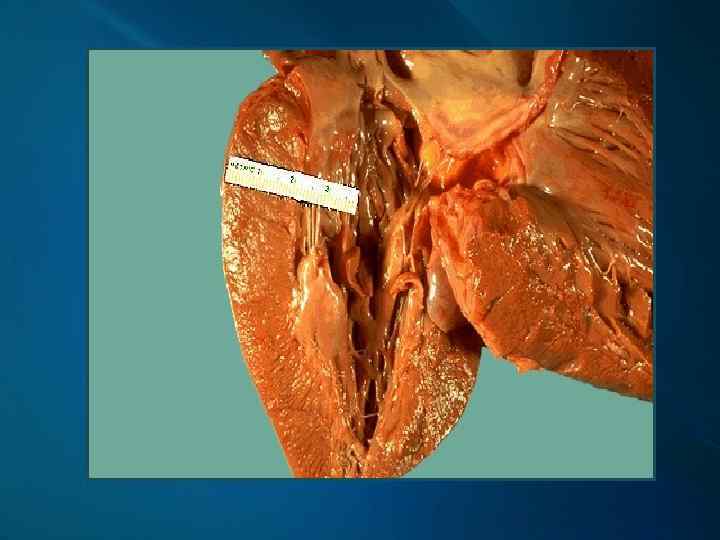

Патоморфология II стадии ГБ МАКРОСКОПИЧЕСКИ: атеросклероз крупных артерий, более выраженный, чем у больных без гипертонической болезни гипертрофия миокарда

Макропрепарат сердца при гипертонической болезни: гипертрофия миокарда стенки левого желудочка